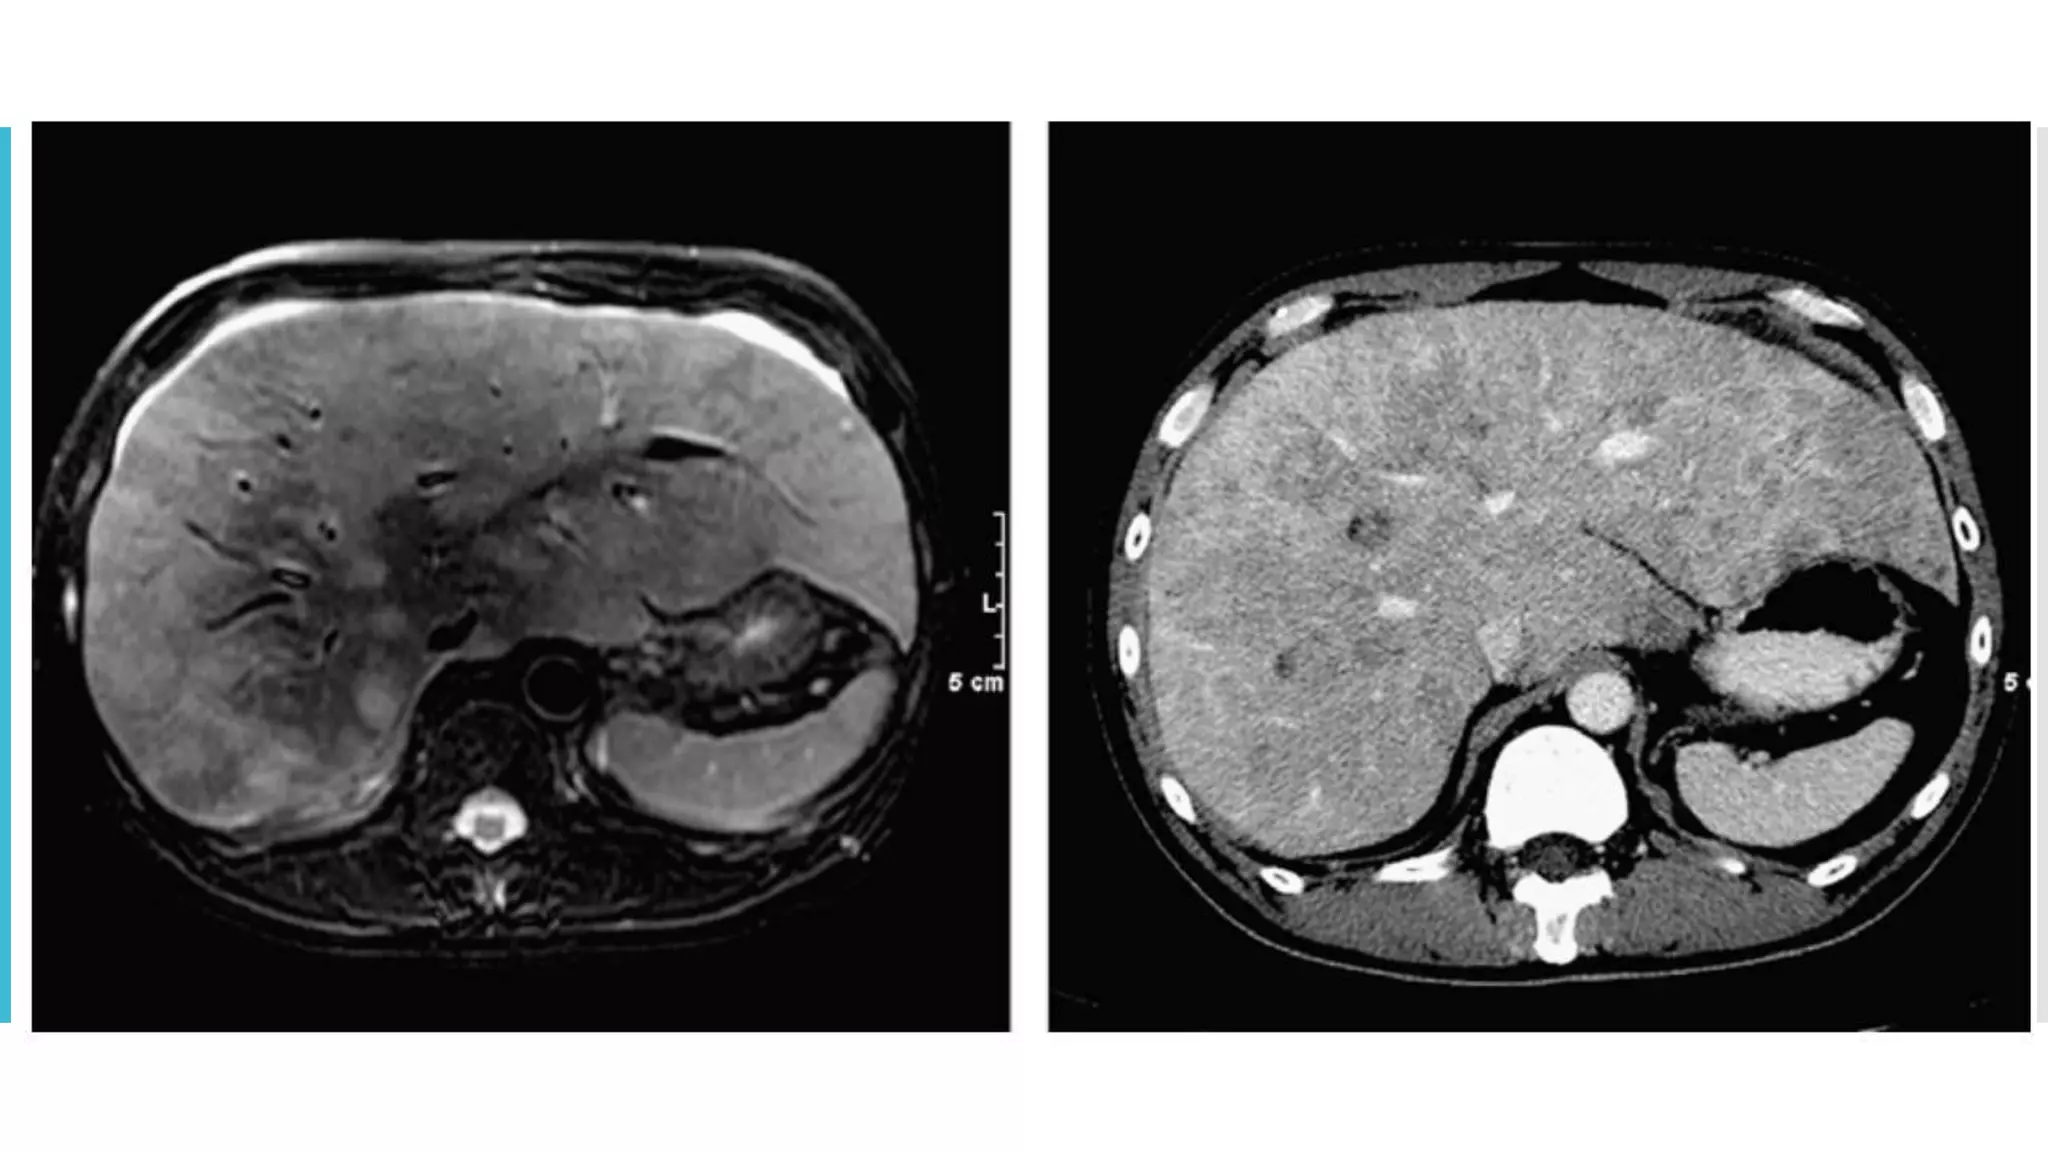

 Recommend triphasic CT for hepatocellular and neuroendocrine

IV contrast administration  Doseand rate as well as timing of scanning should be standardized  Recommend triphasic CT for hepatocellular and neuroendocrine tumors  If contraindication present (think of using non contrst or MRI), should be guided by the tumour type under investigation and the anatomic location of the disease.